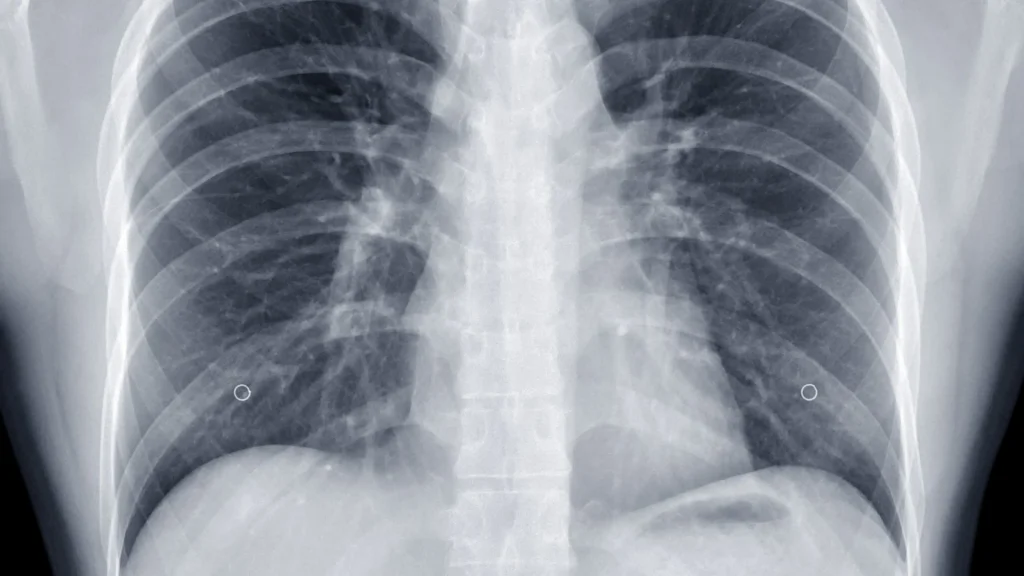

Kualitas Gambar Konsisten di Ruang Terbatas

Meski dilakukan di ruang yang sempit dan penuh perangkat medis, DR wireless tetap mampu menghasilkan gambar dengan kualitas tinggi. Flat panel detector modern memberikan sensitivitas optimal sehingga citra tetap jelas meskipun kondisi cahaya dan posisi pasien kurang ideal. Konsistensi kualitas ini mendukung evaluasi diagnostik yang lebih akurat.